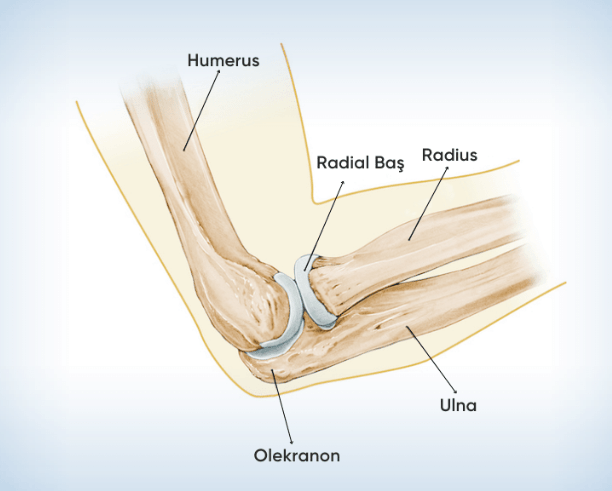

Dirsek Kırığı

Dirsek kırığı, dirsek eklemi vücudun en karmaşık eklerinden biridir. Dirsek kırıkları ise, el üzerine şiddetli şekilde düşme, dirseğe gelen direkt darbeler ve yaralanmalar sonucunda oluşur. Bu tip travmalarda kırık oluşmasa dahi incinme, bağ kopmaları ve çıkıklar oluşabilir. Dirsek Kırığı Belirtileri Şikâyetin birçok belirtisi bulunmaktadır. Bunlar arasında en sık rastlanılanı ise şunlardır: Dirsek

Golfçü Dirseği (Medial Epikondilit) Nedir?

Golfçü dirseği, dirseğin iç kısmında yer alan kemik çıkıntısında ağrı ve hassasiyet ile hissedilen bir rahatsızlıktır. Dirsek eklemi, kolun üst kısmındaki humerus ile alt kısmındaki ulna kemiği arasında yer almaktadır. Humerusun altındaki kemik çıkıntılara epikondil adı verilmektedir. Bunlardan iç tarafta yer alan ise “medial epikondil” olarak isimlendirilir. Golfçü dirseği, daha

Tenisçi Dirseği (Lateral Epikondilit) Nedir?

Tenisçi dirseği, dirseğimizde üç kemik bir araya gelerek bir eklem oluşturur. Bu kemikler, kol kemiğinin alt ucu ve ön kol kemiklerinin üst uçlarıdır. Dirseğe arkadan bakıldığında ise üç belirgin çıkıntı